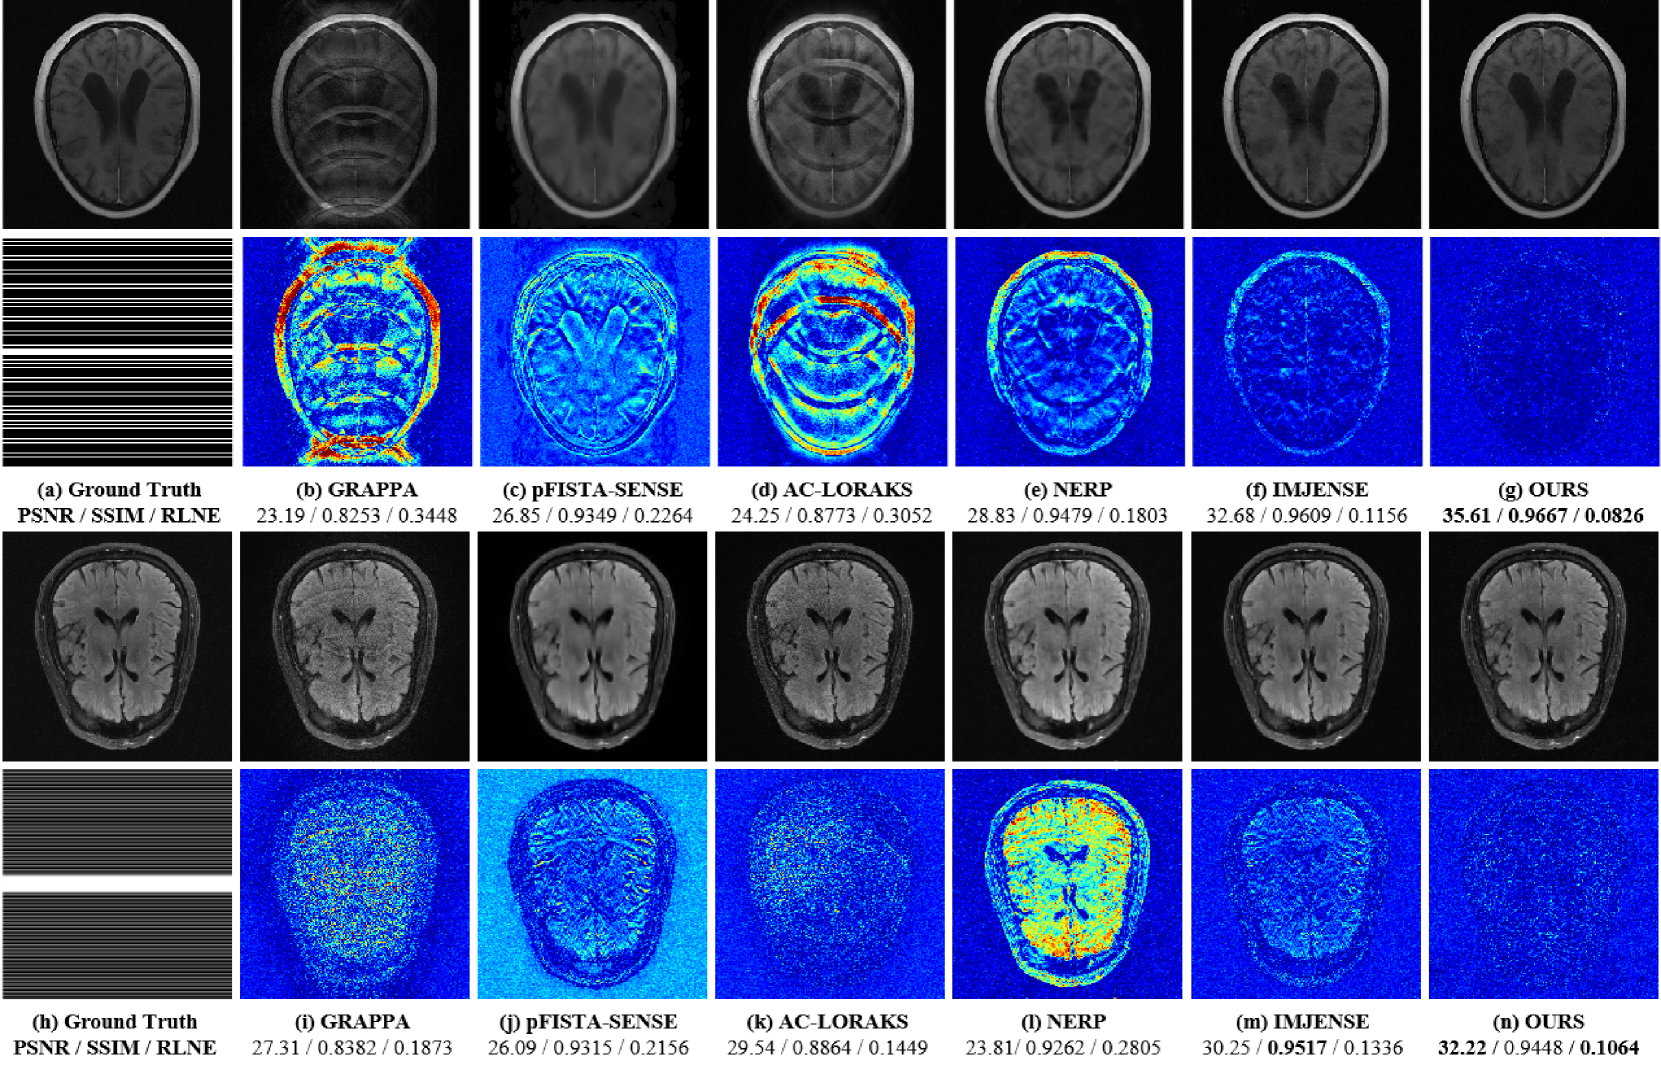

Figure 4: Reconstruction results of different methods based on Dataset \@slowromancapi@ and Dataset \@slowromancapii@. (a) (or (h)) shows the fully sampled image for Dataset \@slowromancapi@ (or Dataset \@slowromancapii@) and the corresponding sampling mask with ACS = 24, R = 5 (ACS = 8). (b)-(g) (or (i)-(n)) show the reconstructed Dataset \@slowromancapi@ (or Dataset \@slowromancapii@) images for different methods along with the corresponding error maps (5x). Below each reconstructed image, the evaluation metrics PSNR/ SSIM/ RLNE are listed, with the best data highlighted in bold.

In the experiments with Dataset \@slowromancapi@ and Dataset \@slowromancapii@ (Fig. 4), GRAPPA and pFISTA-SENSE fail to reconstruct high-quality images especially when ACS is limited. This is expected, as both methods heavily rely on ACS data to estimate sensitivity maps or interpolation kernels, and insufficient ACS data leads to incomplete calibration. Although NERP and AC-LORAKS manage to recover the overall structure, their reconstructions still exhibit noticeable artifacts. These artifacts arise from challenges in accurately modeling the underlying signal structure under high undersampling conditions. Both IMJENSE and INR-CRISTAL demonstrate superior artifact suppression. However, INR-CRISTAL demonstrates superior reconstruction fidelity by preserving finer image details and yielding lower residual errors, as reflected in its more compact and less noisy residual maps. This advantage is further corroborated by the quantitative metrics, where INR-CRISTAL achieves the highest PSNR and SSIM values and the lowest RLNE, highlighting its ability to balance artifact suppression and structural fidelity effectively.